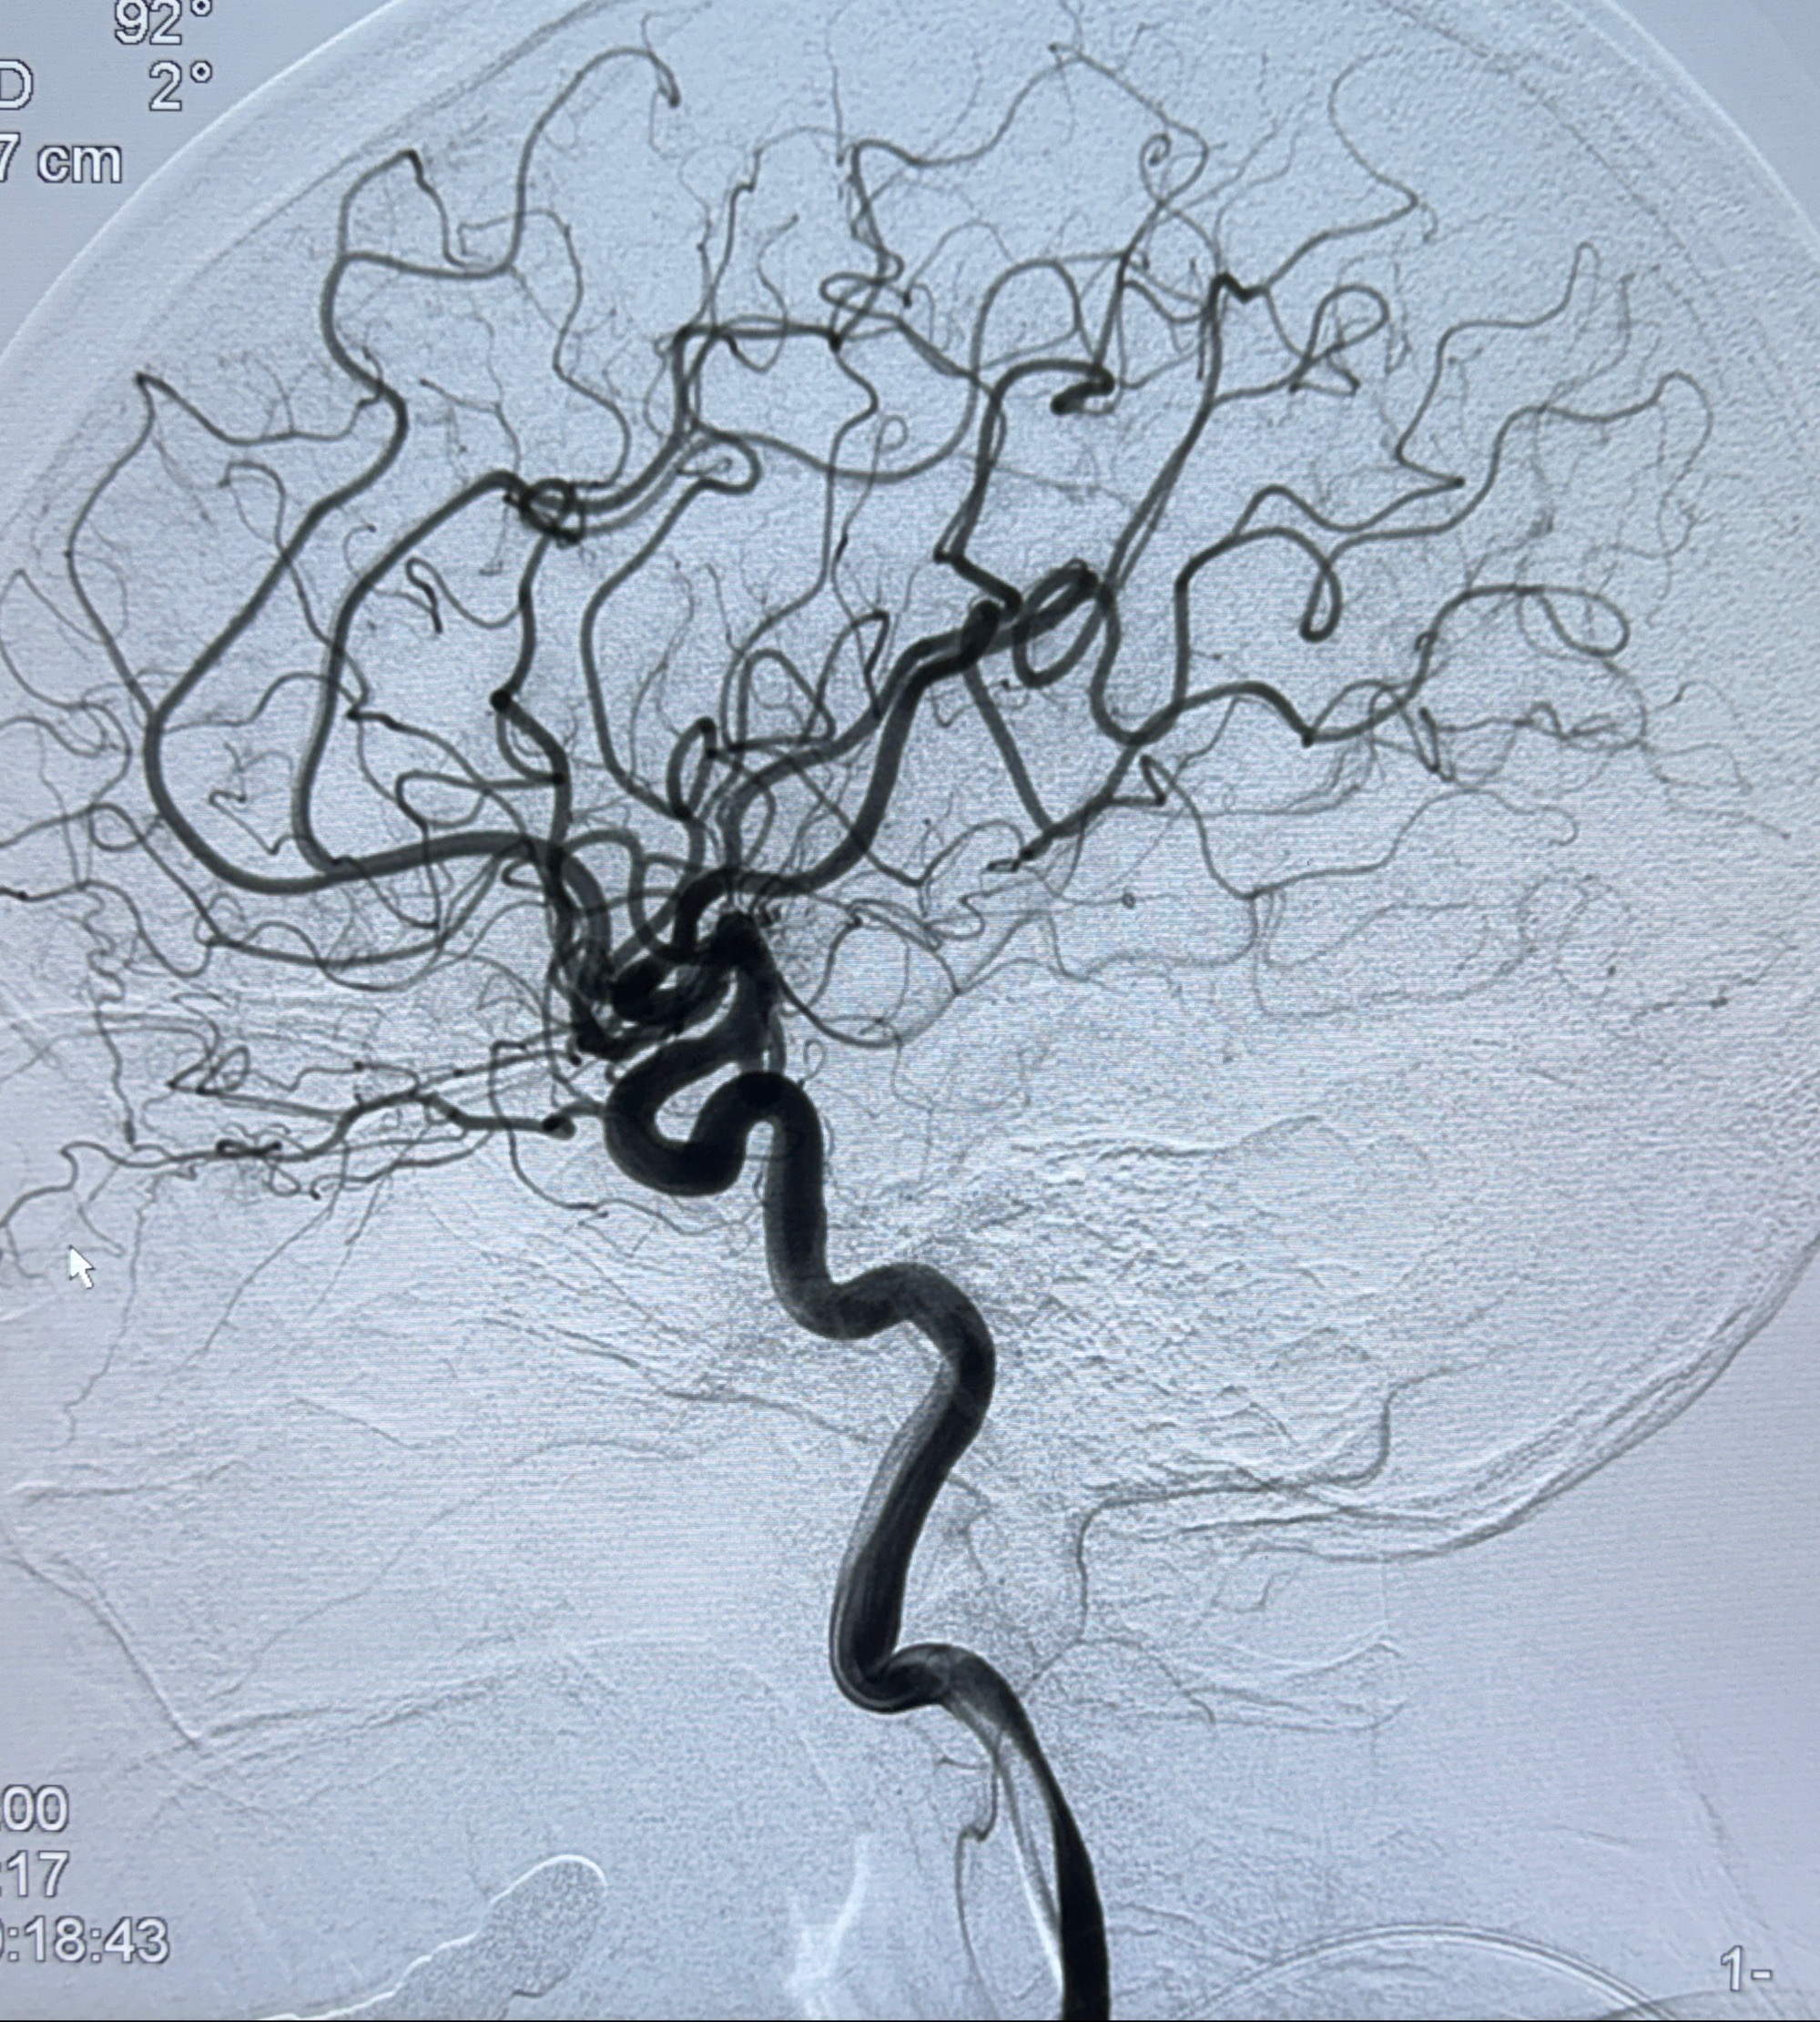

2023-12-04全麻下行支架辅助治疗

S-AB4-20mm

麻醉苏醒佳,遵嘱动作